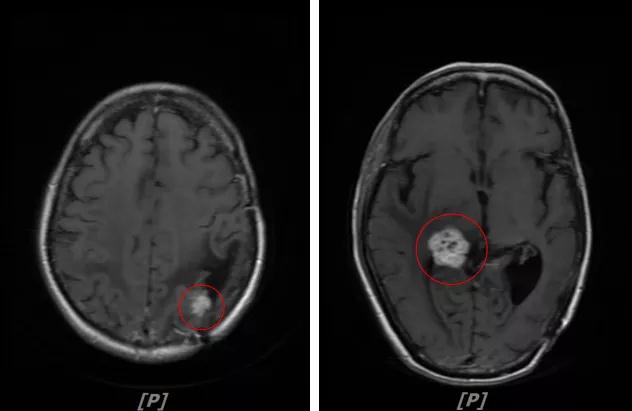

b.2014年3月全脑放疗结束后,予以LX方案治疗(拉帕替尼 1250mg qd+卡培他滨 1500mg bid)。每3个月规律复查,未见明显异常。下图为2014年6月患者行头颅增强MR检查,提示左顶叶脑转移瘤术后改变。

每3个月规律复查,未见明显异常。如2015年8月 头颅MR检查,提示:左顶叶脑转移瘤术后放疗后改变,对比前片2015年3月10日相仿。